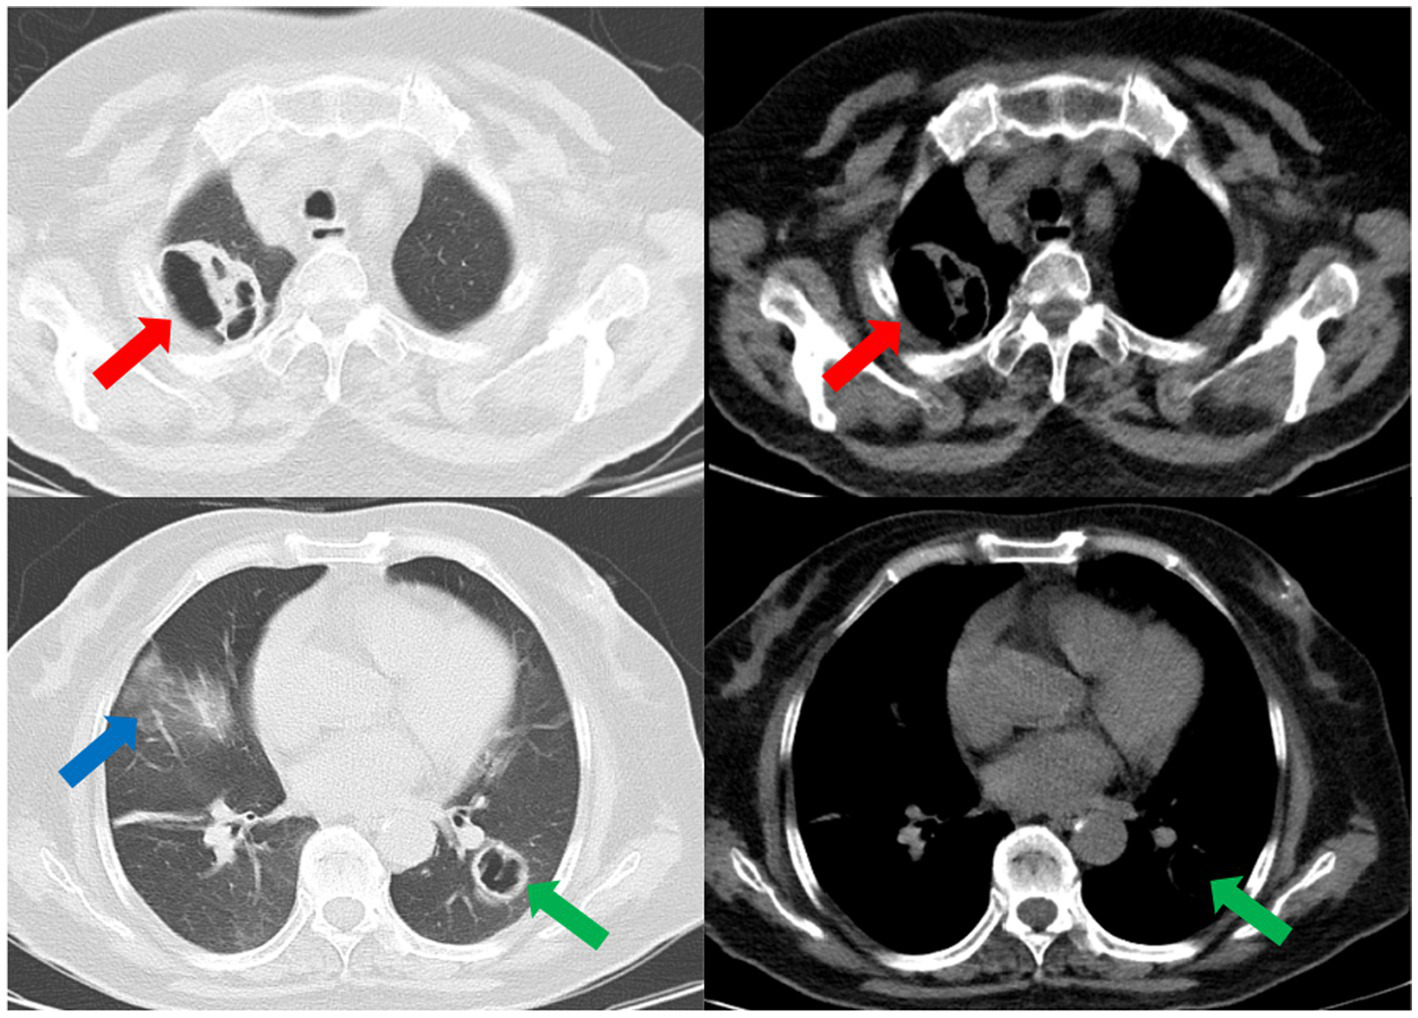

Subsequently, a bronchoscopy with bronchoalveolar lavage was performed on the fourth day after admission. Bronchoalveolar lavage fluid (BALF) was sent to Jiangsu Simcere Medical Diagnostics Co., Ltd., and then metagenomic next-generation sequencing (mNGS) was performed on the Illumina next-generation high-throughput sequencing platform. For detailed methodological description, please refer to State Key Laboratory of Translational Medicine and Innovative Drug Development & Jiangsu Simcere Diagnostics Co., Ltd. previously published paper (5). The mNGS results on the 5th day after admission showed that 17,667 original sequences of Legionella pneumophila were identified, with a relative abundance of 98.3% and a coverage of 7.22% (Figure 3). Meanwhile, a number of other pathogens have been identified, including certain fungi and bacteria (Table 1). After our analysis, we are more inclined to classify them as respiratory custom flora or background flora derived from the environment or samples, regardless of considering them as pathogenic bacteria. On the same day, a repeated CT scan revealed the presence of bilateral lung cavities (Figure 4). These findings were consistent with LP. Immediate treatment with moxifloxacin injection at a dosage of 0.4 g daily was initiated. After 3 days, the patient’s fever resolved, and there was improvement in cough symptoms. A follow-up CT scan 2 weeks later showed that the cavity in the right lung was smaller. Although the cavity in the left lung was slightly enlarged, the walls of the cavity were thinner, and the infiltration from both lungs had been resolved (Figure 5).

Figure 4

www.frontiersin.org

Figure 4. The repeated CT scan conducted on the fourth day after admission showed cavitary lesions in both lungs (red arrows and green arrows). Remaining patchy infiltrate in the right lung (blue arrow).

Figure 5

Figure 5. A subsequent CT scan 2 weeks later showed that the cavity in the right lung had decreased in size (red arrow), while the cavity in the left lung had slightly enlarged (green arrow). However, the thickness of the walls of both cavities had diminished, and the bilateral pulmonary infiltration indicated by the blue arrows had been resolved.